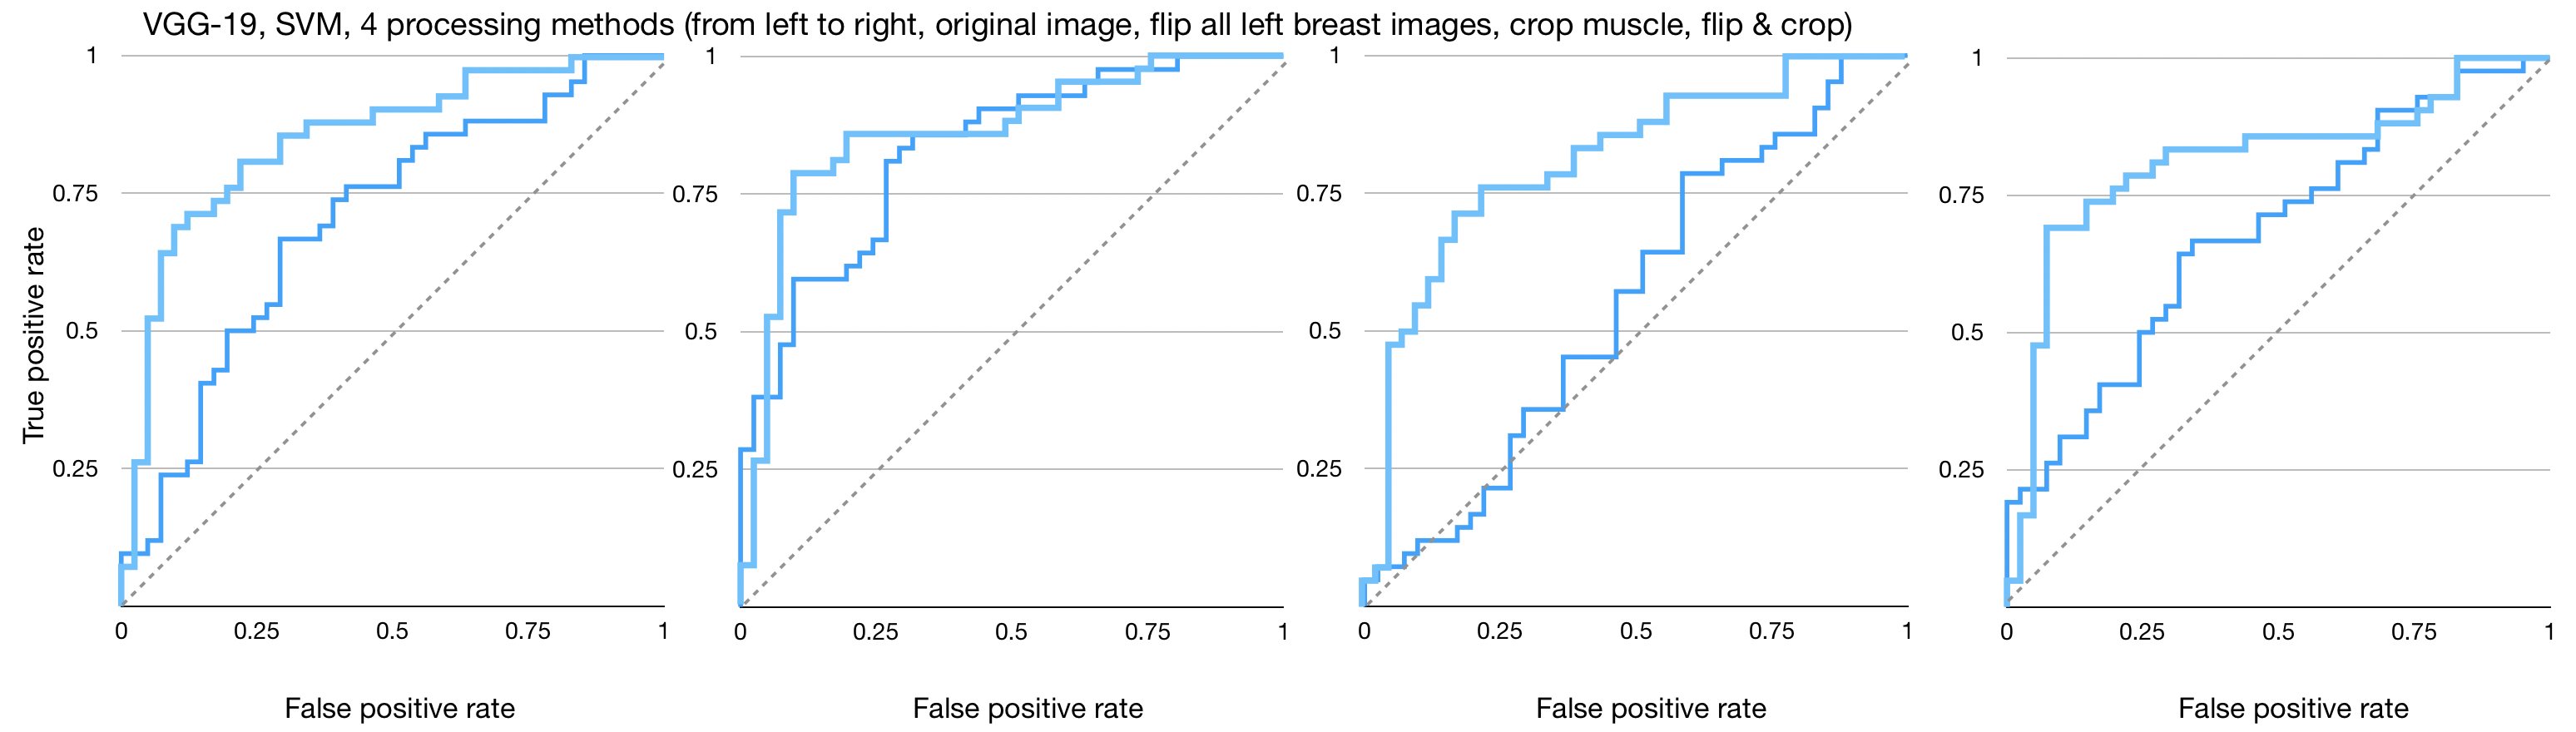

Figures 4, 5, and 6 show the imaging for which both humans and CNNs make mistakes, model introduced errors, and model corrected human errors. Figure 7 shows the receiver operating characteristic curve (ROC curve) for each of the 16 end-to-end models between the CNNs and radiologist gist plus CNNs. Tables 1 and 2 show the AUC data and differences used in the main text from the 16 conditions we have tested. Although the present work provides knowledge about adding radiologists’ data into CNN, it does not allow for training on new data, thus restricting our application domain to a small range of in-house data.